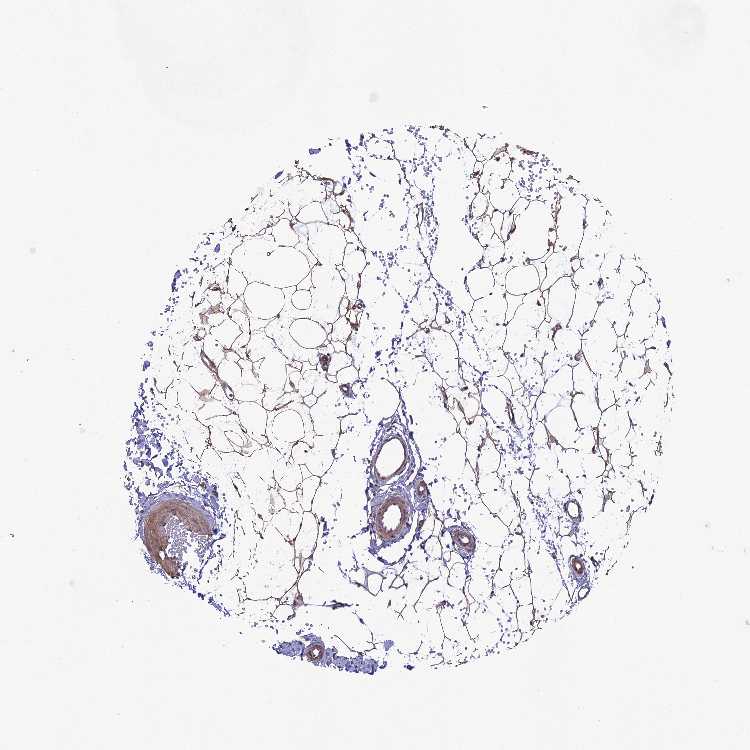

SOFT TISSUE 1 - Antibody stainingi

Antibody staining in the annotated cell types in the current human tissue is reported as not detected, low, medium, or high, based on conventional immunohistochemistry profiling in selected tissues. This score is based on the combination of the staining intensity and fraction of stained cells.

Each image is clickable and will lead to virtual microscopy that enables deeper exploration of all samples and also displays staining intensity scores, fraction scores and subcellular localization as well as patient and tissue information for each sample.

Antibody HPA036089Antibody HPA036090Antibody CAB018774

Chondrocytes -Not detectedLow

Fibroblasts Not detectedLowMedium

Peripheral nerve Not detected-Not detected

SOFT TISSUE 2 - Antibody stainingi

Peripheral nerve Not detectedMedium-